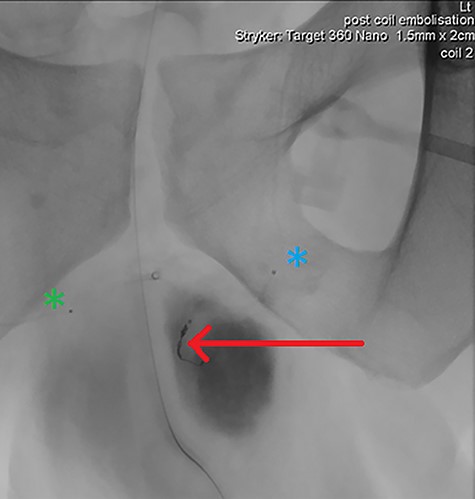

Final intraoperative fluoroscopic image demonstrating microcoil placement (red arrow); note the microcatheter placement within the left (blue asterix) and right (green asterix) distal branches of bilateral internal pudendal arteries for reference